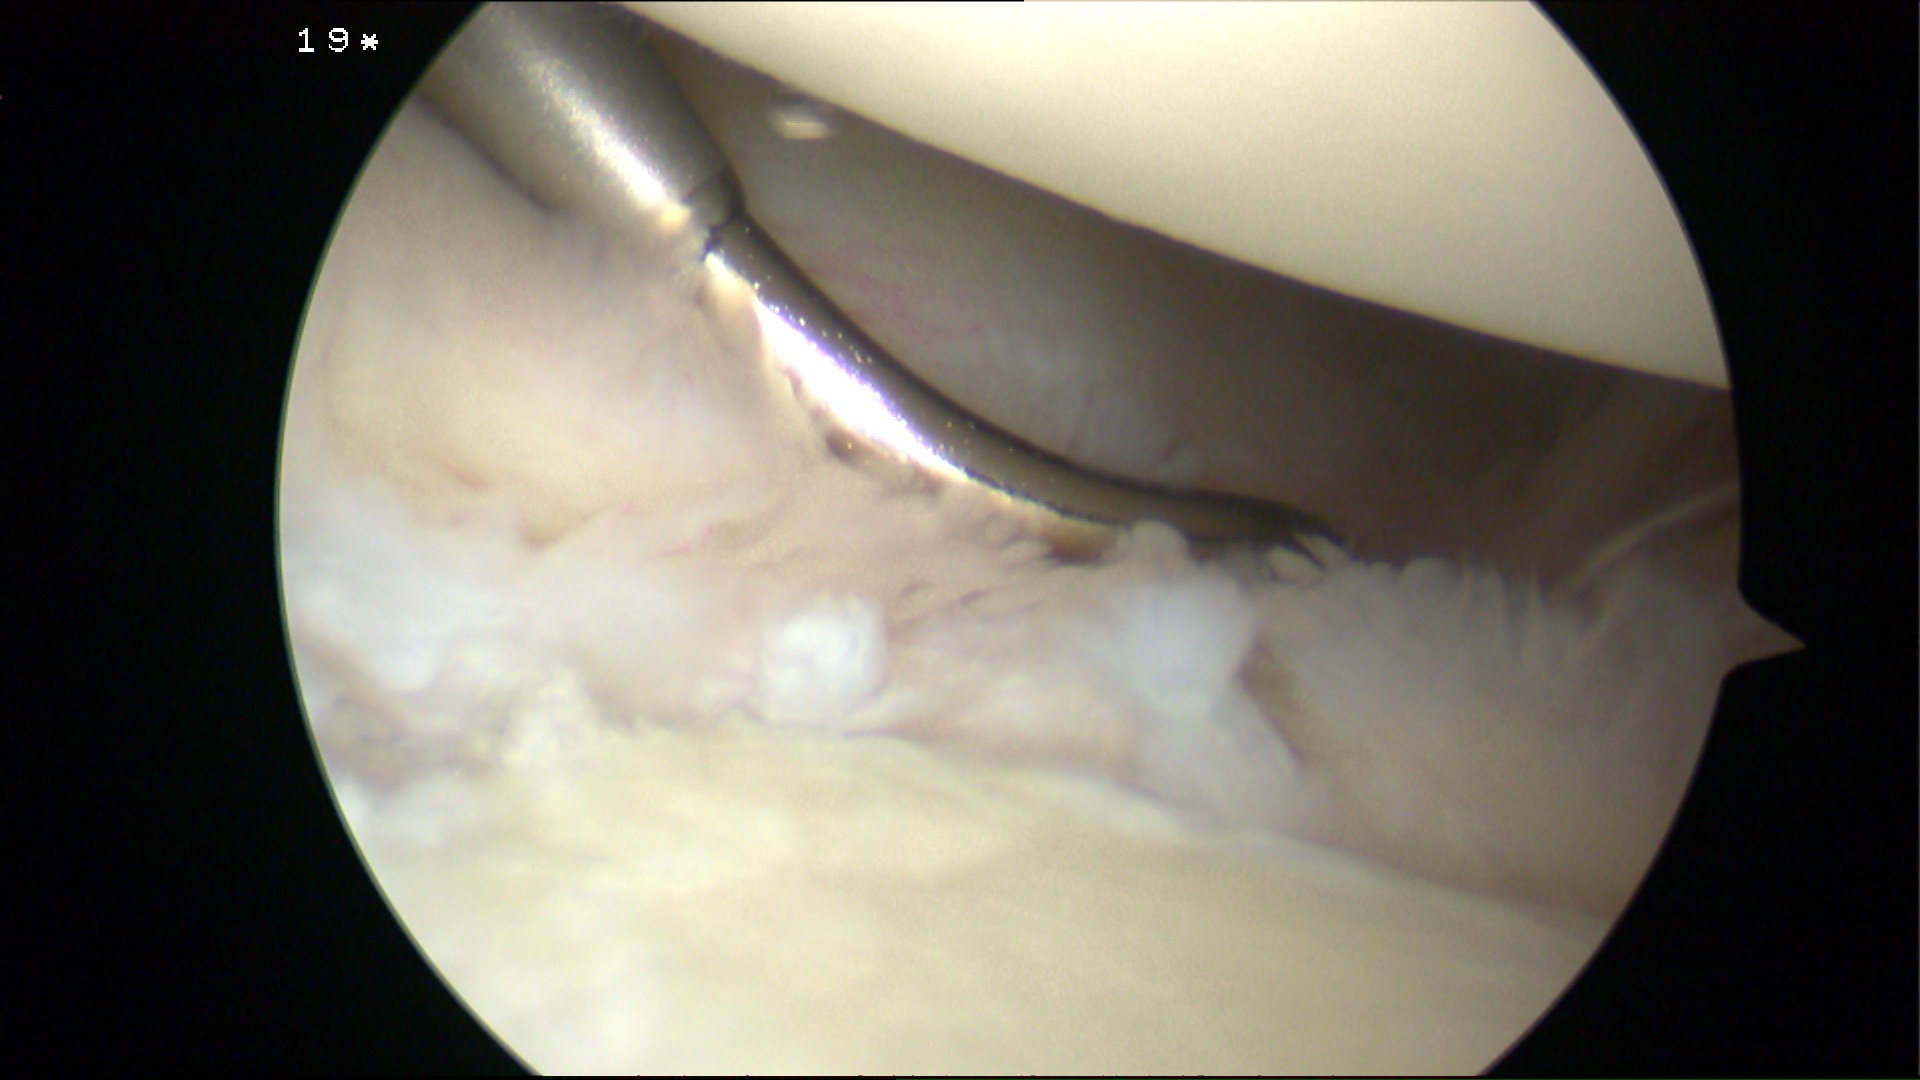

Glenoid assessment

Anterior chondral damage

Anterior glenoid bone loss

Hill Sachs lesion

Debride anterior glenoid bone to bleeding bone